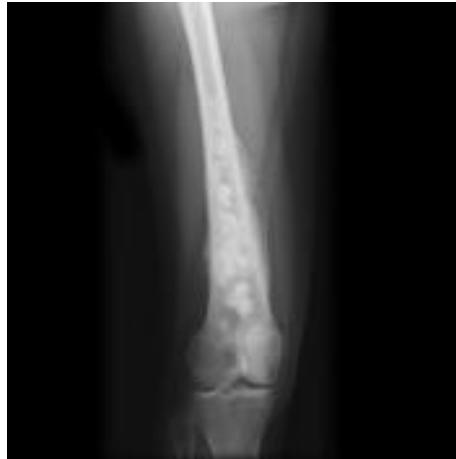

AP lat x-ray

- Site: multiple small Right femu, metaphysis, ddiaphysis

- Size: varying sizes lesions on humerous

- Matrix: Multiple lesions, mixed

- Zone of transition: wide zone transition,

- Bone effect: cortical destruction, periostea reactions

- Soft tissue: periosteal reaction

malignant